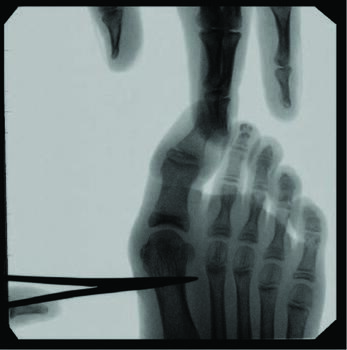

When we approach surgical correction of hallux valgus, goals include realigning the hallux joint across all three planes, improving the first intermetatarsal angle, restoring and maintaining a pain-free joint, improving cosmesis, and allowing a return to comfortable shoes. Inclusion criteria for surgery that we consider include intact vasculature, Vitamin D-25 levels above 40 nmol/dl, and medical stability in the presence of comorbidities. Percutaneous hallux valgus correction has indication for spastic or non-spastic bunions, revisions, and a wide range of intermetarsal angles. Other exclusion considerations include patients with severe osteoarthritis or osteomyelitis near the first metatarsophalangeal joint.

In a study comparing MIS to distal chevron metatarsal osteotomy bunion correction in a population of young females, there were no statistically significant outcomes in postoperative radiographic measurements of hallux valgus angle, DMAA, sesamoid position, first metatarsal length, and relative second metatarsal length.15 Clinical scores significantly increased postoperatively in both groups, with higher cosmesis satisfaction rates and a shorter operative time in the MIS group. This study found that the most significant complication in the MIS group was revision due to osteotomy site irritation occurring about three months postoperatively, while deformity correction was necessary two years postoperatively in the chevron group.15

Kaufmann and colleagues compared five-year outcomes of open distal metatarsal chevron osteotomies to a minimally invasive approach, finding comparable satisfaction as well as radiographic and clinical outcomes in both groups.16 More recently, Neufeld and team reported that the minimally invasive chevron and Akin (MICA) procedure achieves reproducible significant correction and high patient satisfaction with early weight-bearing and fast pain score improvement.13 They noted a 5.3 percent reoperation rate due to hardware removal, debridement, and neurolysis, finding no significant increase in nerve injury between the MICA and open procedure groups. The authors also noted significant deformity correction is possible with the third-generation approach of utilizing two bicortical screws.13